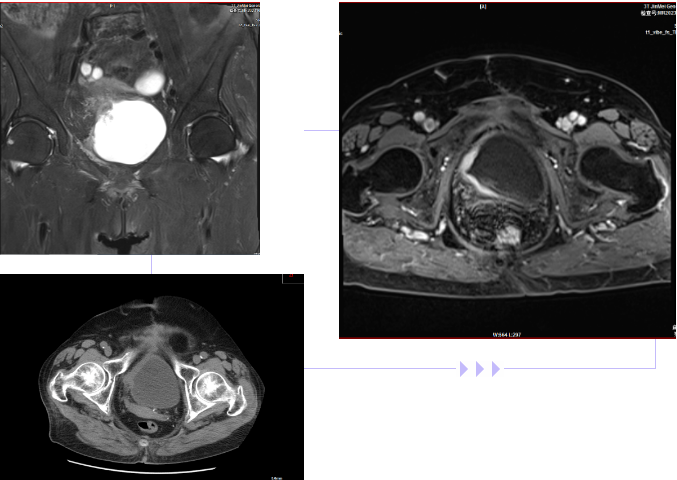

李奶奶(化名)今年73歲高齡,因?yàn)槟蝾l、尿急、間斷發(fā)熱等身體不適,就診于泌尿外科。據(jù)了解,李奶奶曾因膀胱惡性腫瘤,進(jìn)行了“膀胱部分切除術(shù)”。通過(guò)對(duì)認(rèn)真詢問(wèn)病史和詳細(xì)的體格檢查,結(jié)合腹部CT、磁共振等檢查,明確診斷為“膀胱惡性腫瘤術(shù)后復(fù)發(fā)”。

李奶奶年齡較大,屬于高年女性患者,有心肺功能不全、高血壓、腦梗死、糖尿病等多種基礎(chǔ)病,曾有膀胱腫瘤手術(shù)史,加大了術(shù)中解剖分離難度,若行手術(shù)治療,風(fēng)險(xiǎn)極大。

術(shù)后極有可能出現(xiàn)出血、感染、愈合不良合并尿漏、淋巴漏等風(fēng)險(xiǎn),進(jìn)而導(dǎo)致嚴(yán)重后果。如果不及時(shí)進(jìn)行手術(shù)治療,膀胱惡性腫瘤持續(xù)進(jìn)展,等待患者的只有生命的消逝。